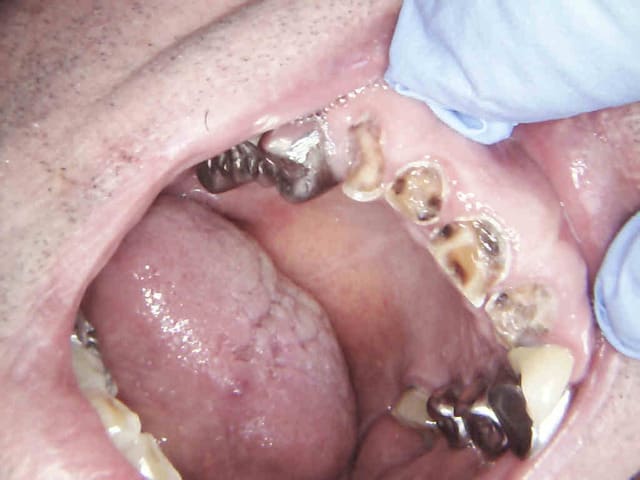

Cas ci dessous endo taille provisoire empreinte 13,12,11,21 dans une séance de 2H 30, Pose IC ceram 13 12 11 21 endo 35, 36 1H 30 ( tronculaire avant de poser), Taille 35, 36 1H, Pose IC 35 36 ext 46 (tronculaire avant de poser) une demi heure.

1 buuxho - Eugenol

3 myduts - Eugenol